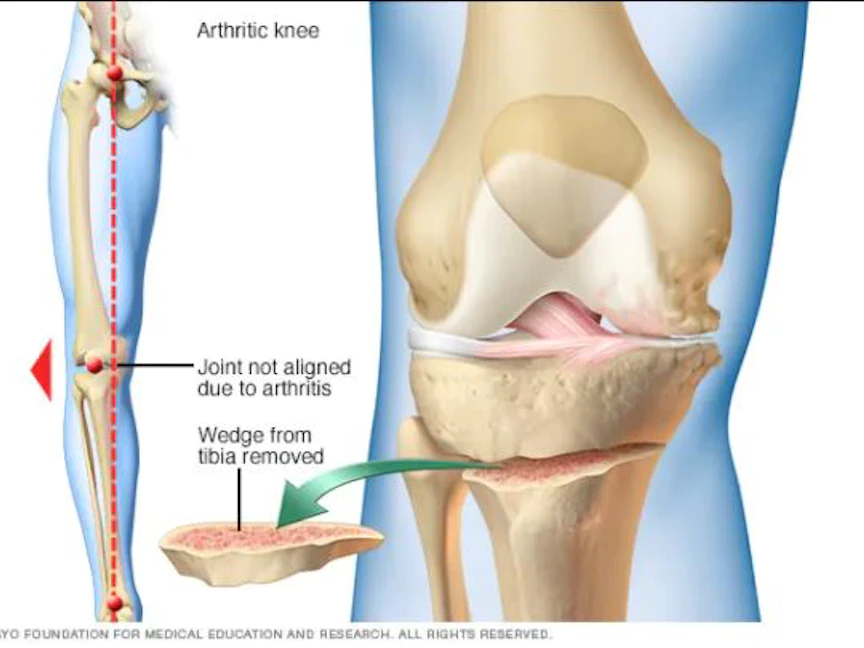

ويشمل الإجراء إزالة أو إضافة قطعة من العظم لعظم الساق (القصبة) لديك أو عظم الفخذ للمساعدة على نقل وزن الجسم بعيداً عن الجزء التالف من مفصل ركبتك.

وعندما يتآكل الغضروف على نحوٍ غير مستوٍ، فإنه يضيِّق المسافة بين عظم الفخذ والقصبة، ما يتسبب في تقوس الركبة للداخل أو للخارج حسب الجانب المتضرر من الركبة.

وبحسب مكان التلف، قد تتضمن الجراحة عظم الظنبوب أو عظم الفخذ. ينطوي النوع الأكثر شيوعاً من قطع العظم على عظم الظنبوب.

يتمثل الخيار الآخر في قطع عظم الظنبوب أو عظم الفخذ ثم إزالة وتد العظام. يتم تجميع حواف قطع العظام وتركيبها في موضعها باستخدام جهاز معدني. يُطلق على ذلك إغلاق وتد قطع العظام. وعادةً ما تستغرق الجراحة من ساعة إلى ساعتين.